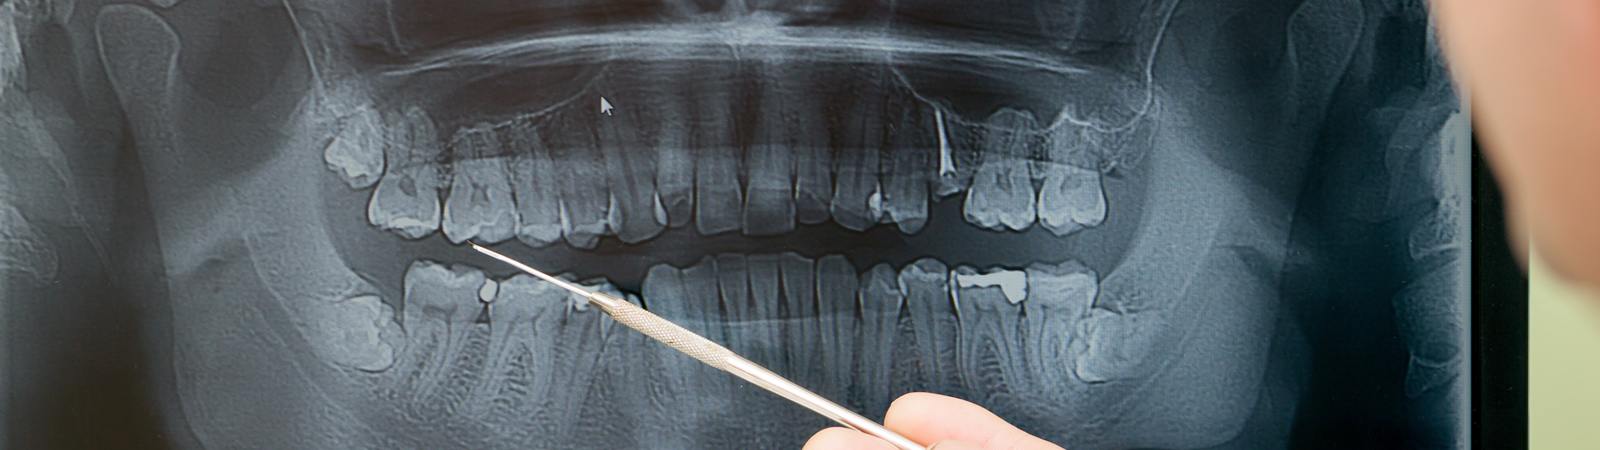

The benefits of dental X-rays are huge. Radiographs are a very important part of dentistry. Your teeth are embedded in your jaw, so without X-rays we can only see half the story. An image is formed by passing X-rays through an object (e.g. your tooth) onto a plate which is then immediately transmitted into the computer. The digital … Continue reading Digital X-Rays